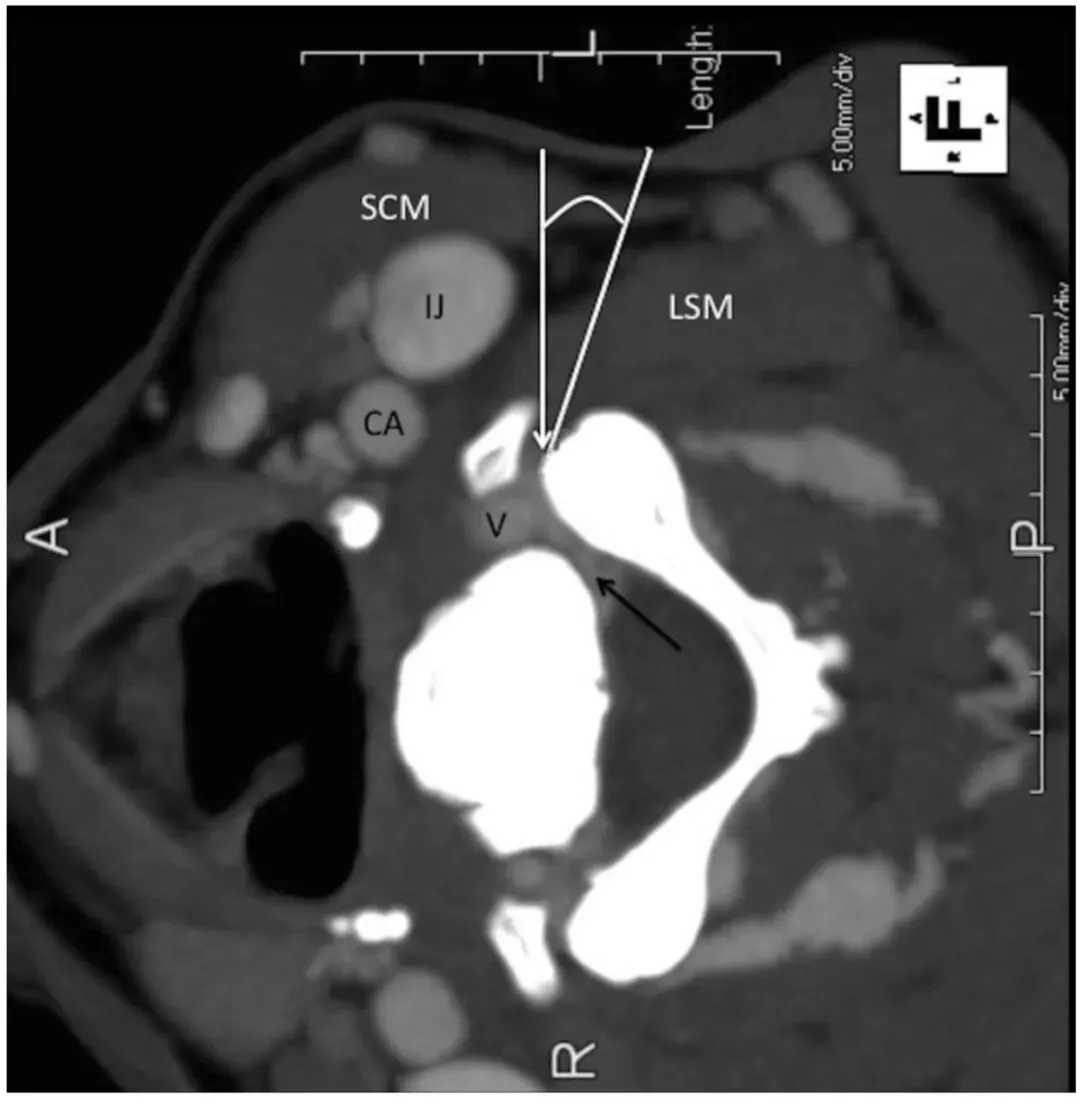

3. 靶点确定:在CT控制台上,靶点设定为受累神经孔处、同侧关节突关节柱的前外侧缘。需同时识别椎动脉并予以避让。

4. 穿刺路径规划:在CT控制台上绘制近乎垂直于靶神经孔的穿刺路径,测量皮肤到靶点的距离。采用侧方入路,垂直地面的进针方向。